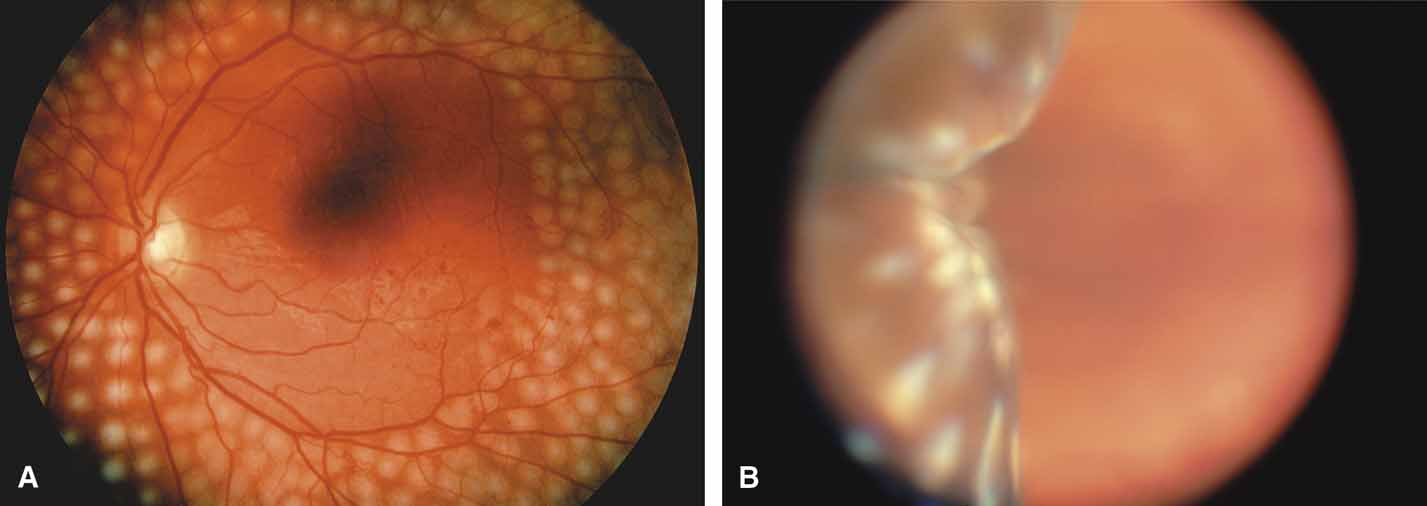

Sturge-Weber Syndrome

The Sturge-Weber Syndrome is a sporadically occurring phakomatosis that consists of a diffuse choroidal hemangioma, facial nevus flammeus (dermal angioma) (Fig. 13), meningeal angioma with “tram-track” calcification of the brain, and an ipsilateral glaucoma often seen when the dermal angioma involves the upper lid (Fig. 14). The glaucoma may present in infancy or the late teens. In infancy, the glaucoma mechanism may be similar to congenital glaucoma (abnormal trabecular bands) and differ from the later-onset form, which may result from elevated episcleral venous pressure.62 Phelps63 demonstrated elevated episcleral venous pressure in this syndrome and related the extent of the episcleral angioma (often more obvious at surgery when conjunctiva was reflected) to the severity of the glaucoma. Recent work demonstrated thickening of the trabecular beams with abnormalities of the outflow structures, possibly induced by the abnormal vasculature present during embryogenesis.64 Regardless of the exact mechanism, most authorities agree that standard filtration methods carry a high risk of expulsive choroidal hemorrhage. If filtra-tion surgery is contemplated, Bellows and co-workers65 recommend prophylactic sclerostomies prior to decompression of the eye to avoid intraoperative choroidal detachments that may occur in these patients, even when choroidal hemangiomas are not present. Meticulous flap closure that avoids hypotony is the mainstay to preventing choroidal detachments.66 Preoperative scatter laser photocoagulation over the hemangioma, even in the absence of serous retinal detachment, may also reduce the risk of choroidal exudation prior to filtration surgery.66